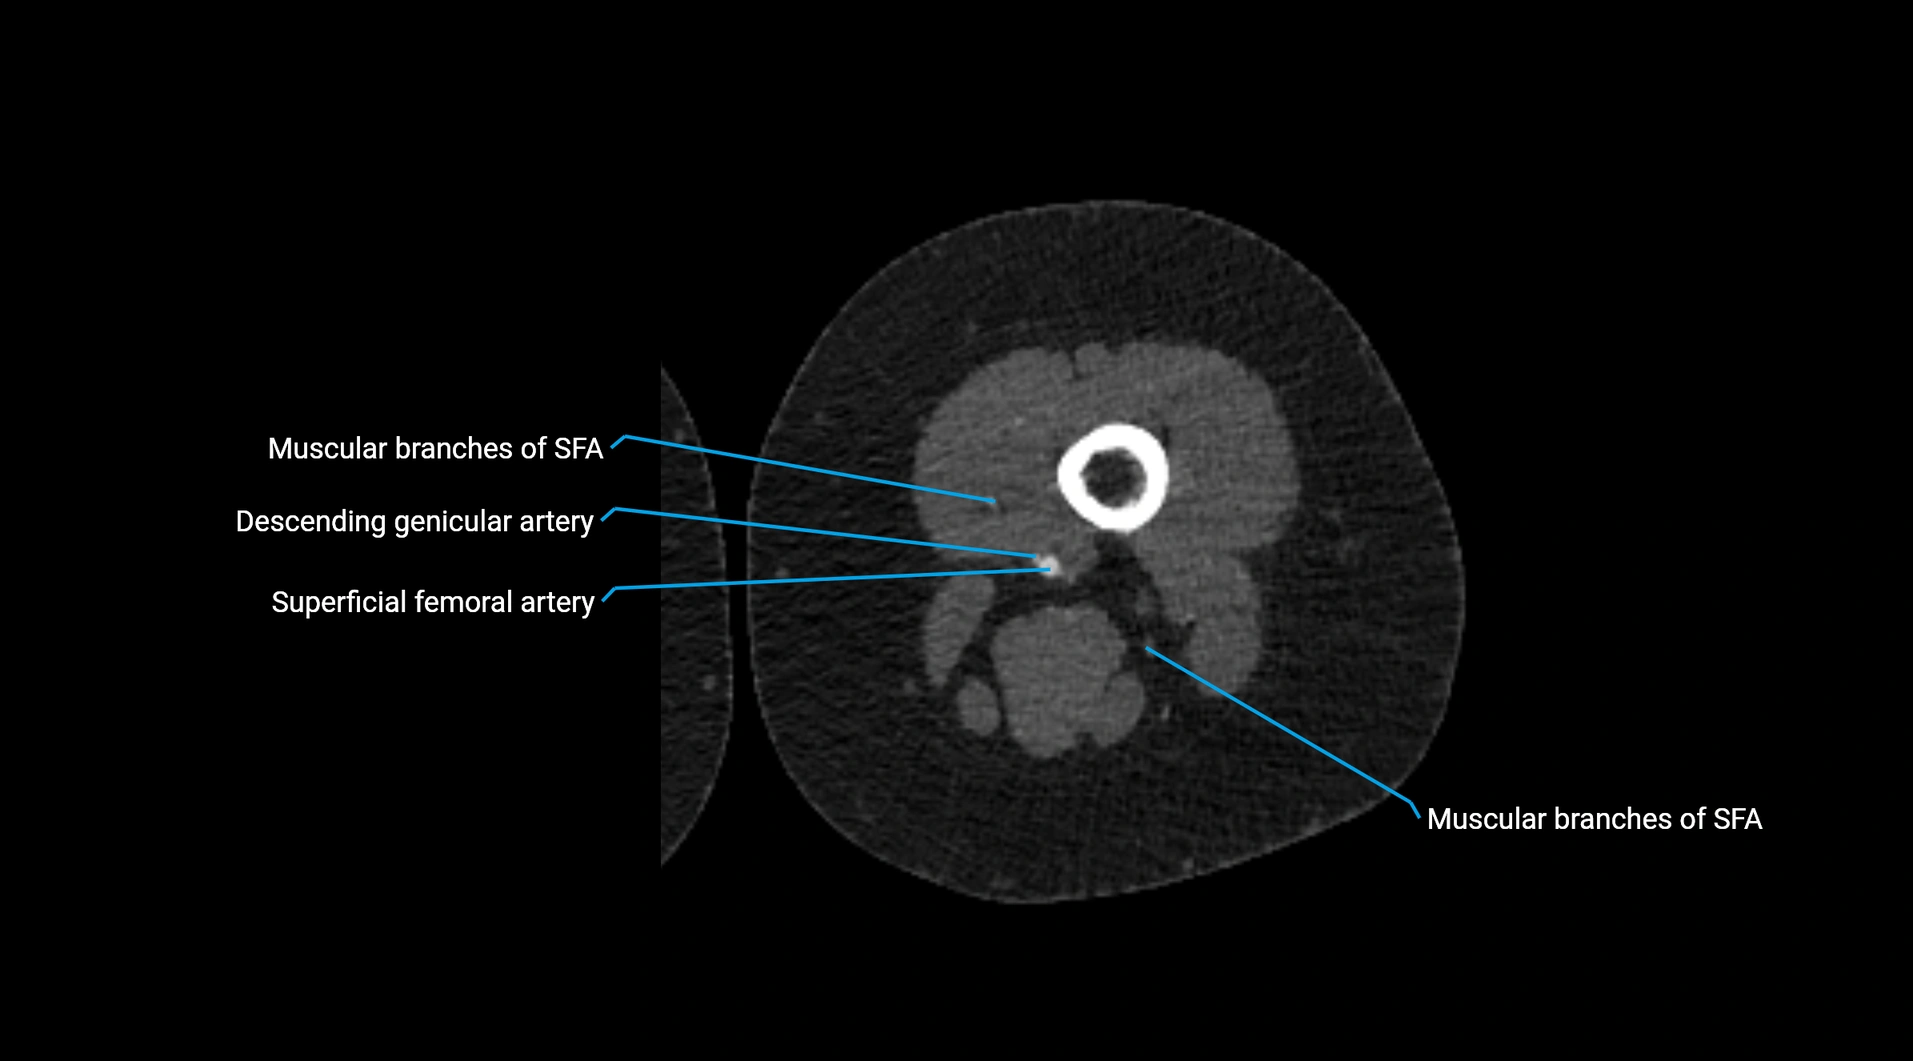

Contrast-enhanced CT (CTA):

• Gold standard for abdominal aortic imaging

• Provides excellent detail of lumen, wall, aneurysm, thrombus, and branch vessels

• Multiplanar and 3D reconstructions help in aneurysm measurement, stent graft planning, and dissection evaluation

• Detects acute rupture, traumatic injury, or occlusion with high sensitivity